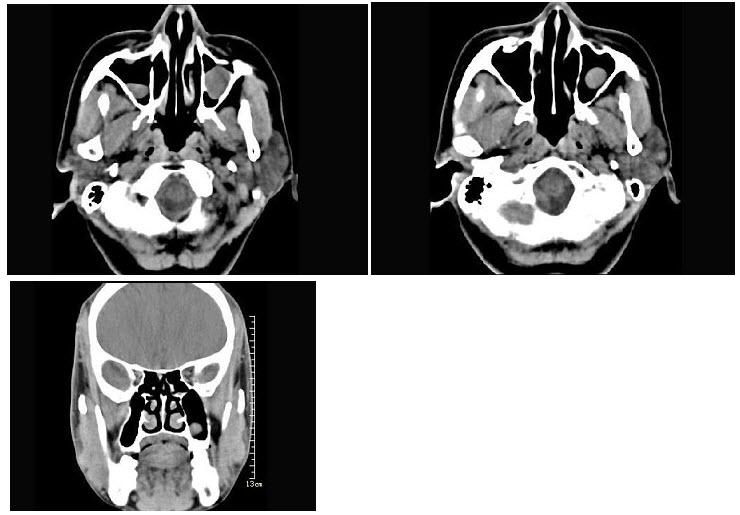

68、单项选择题

女,52岁,头痛、恶心、步态不稳,胸部和颅脑增强CT检查如图,最可能的诊断为()

A.星形细胞瘤

B.脑脓肿

C.肺癌脑转移

D.脑膜瘤

E.脑梗死